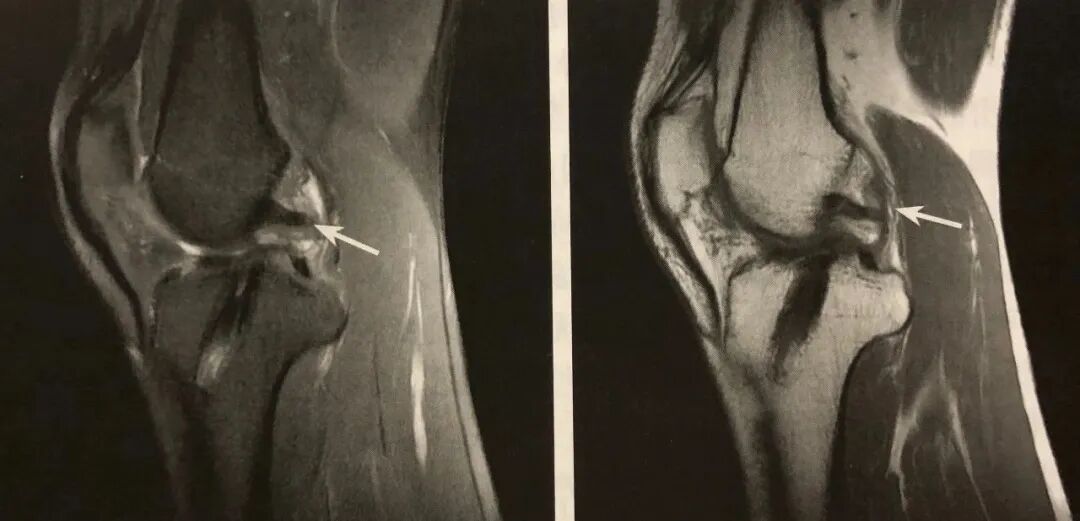

阅片要点:

1. 内侧半月板桶柄状撕裂间接征象;

2. 在 MRI 矢状位观察;

3. 典型表现为两条近似平行的弧形低信号带;

4. 后上方者为后交叉韧带,前下方者为撕裂的半月板内缘碎片;

5. MRI 诊断注意结合病史和排外相关变异。